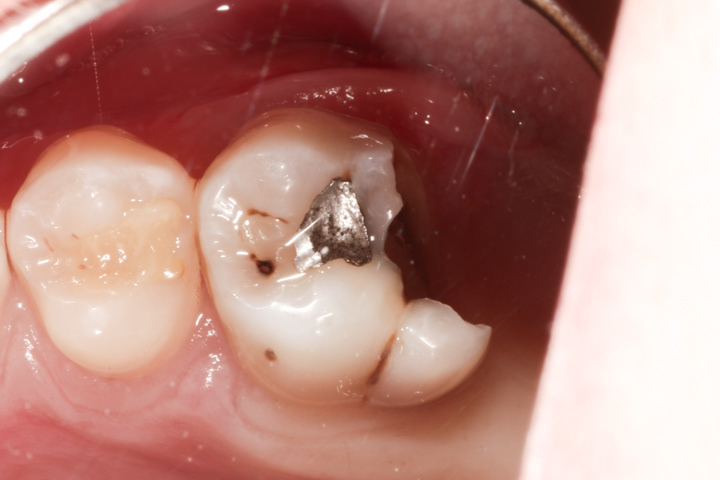

PRZYKŁAD 1

Nieleczona próchnica powoduje niszczenie tkanek zęba. W momencie gdy próchnica dojdzie do komory zęba, dochodzi do infekcji. Najczęściej w tym stadium pojawia się ból samoistny, zapalenie takie jest nieodwracalne, a ząb kwalifikuje się do leczenia kanałowego.